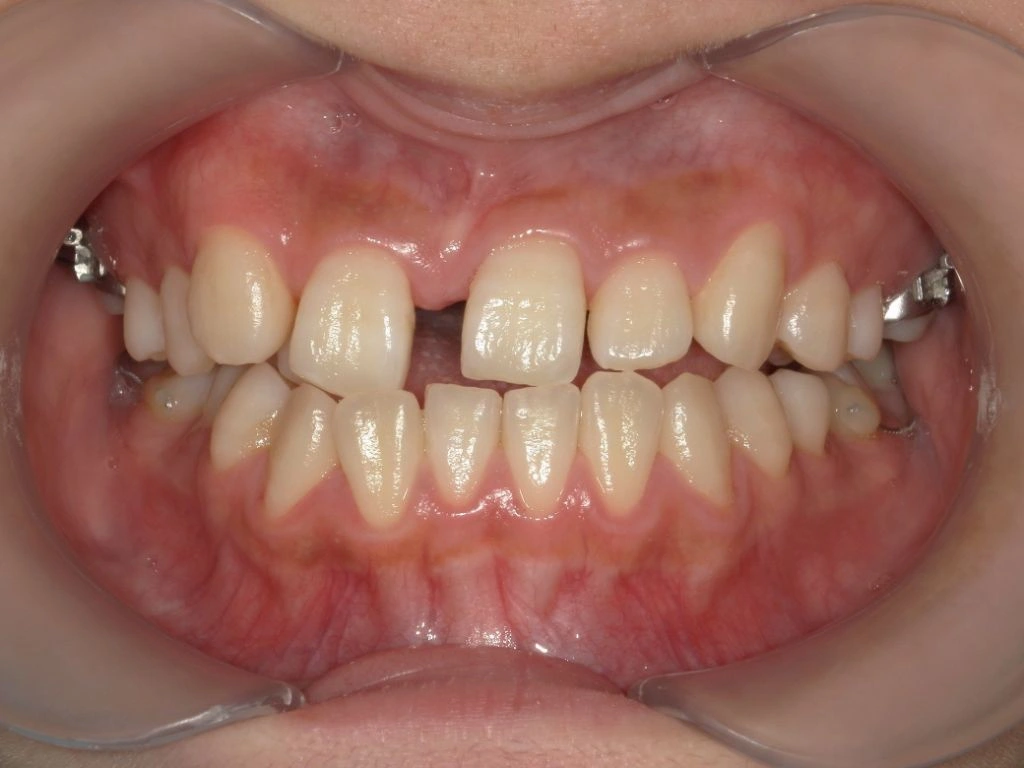

【治療前】

セファロ分析から、明らかに上顎劣成長及び下顎骨の過成長を認めます。MSEの適用症例と判断しました。